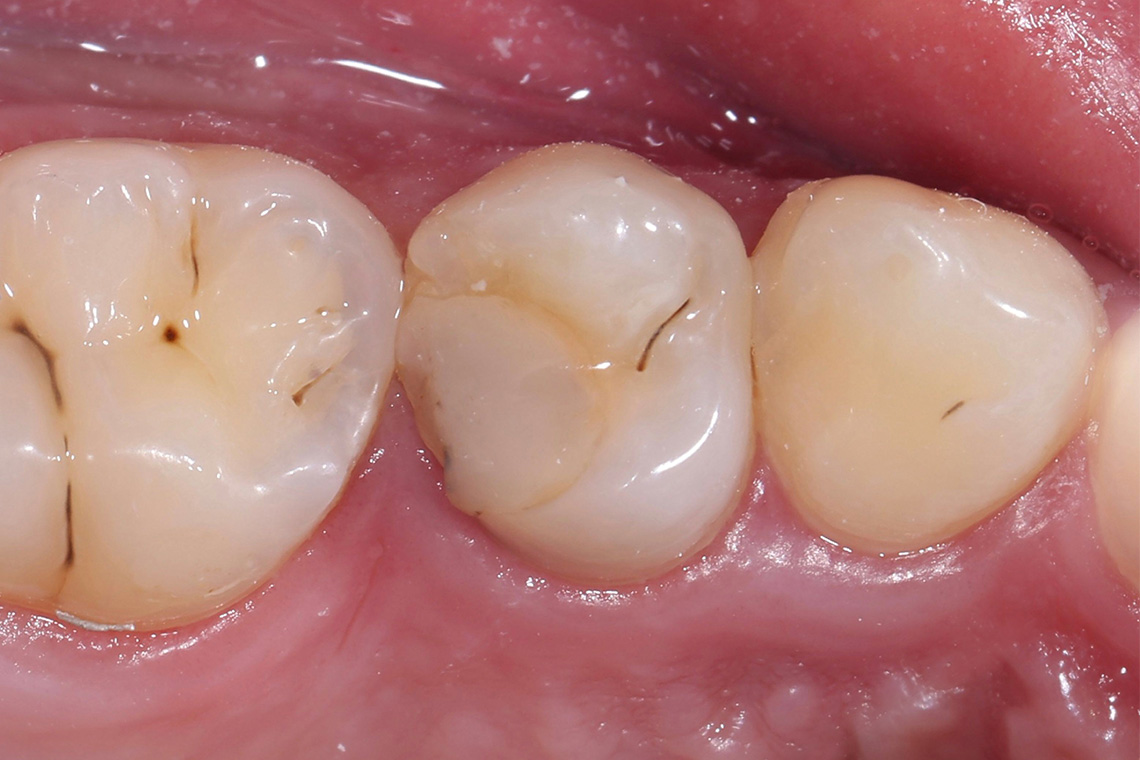

VITA ENAMIC multiColor Endokrone: Ausgangssituation vs. Finales Ergebnis

Ergebnis: VITA ENAMIC multiColor integrierte sich harmonisch in die natürliche Zahnsubstanz. Die insuffiziente Kompositfüllung an Zahn 14 (od) hatte zu Entzündungen im Zahnzwischenraum geführt.